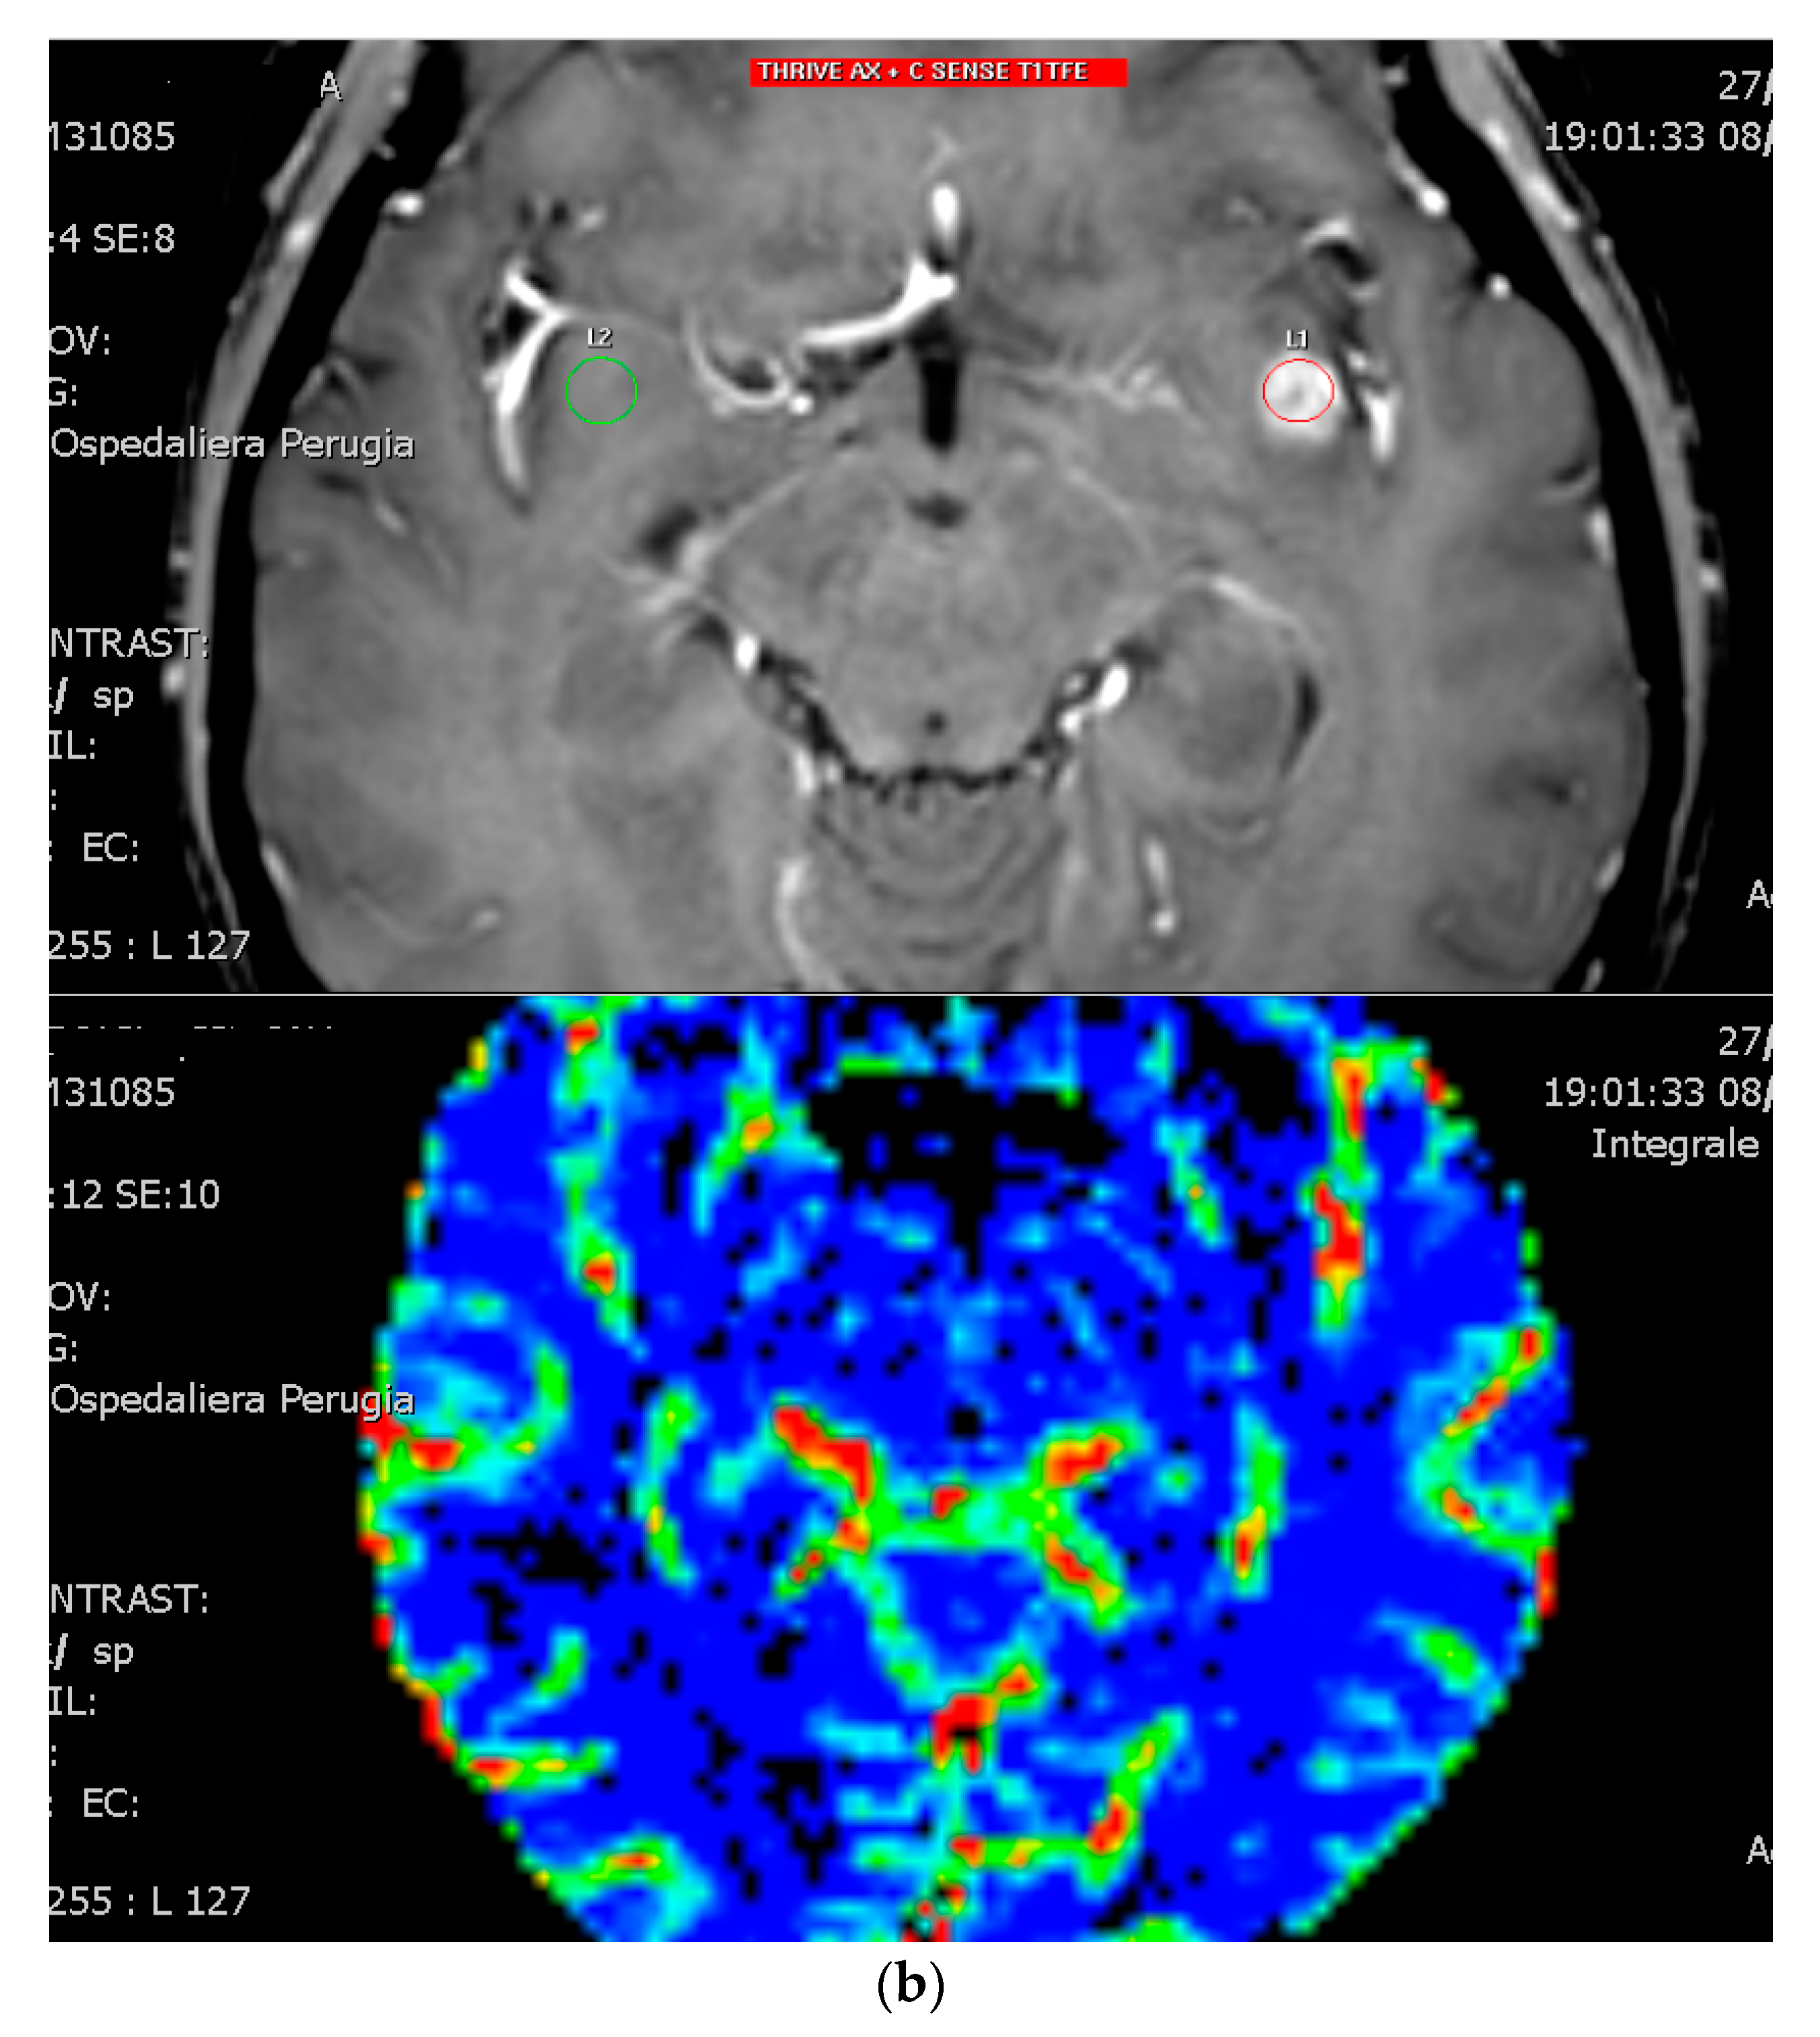

3.1. Diagnostic Imaging Tools in Radionecrosis

3.2. Diffusion and Perfusion MRI